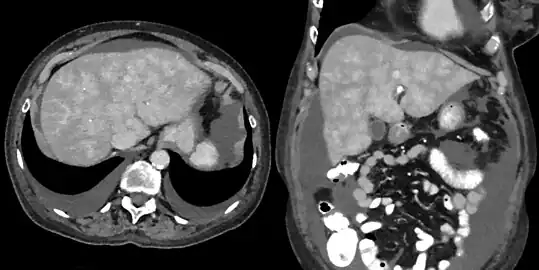

CT appearance of liver in congestive hepatopathy, sometimes referred to as a nutmeg liver. Due to congestion, contrast does not flow through the liver in a normal manner. Axial and coronal images in the portal venous phase.